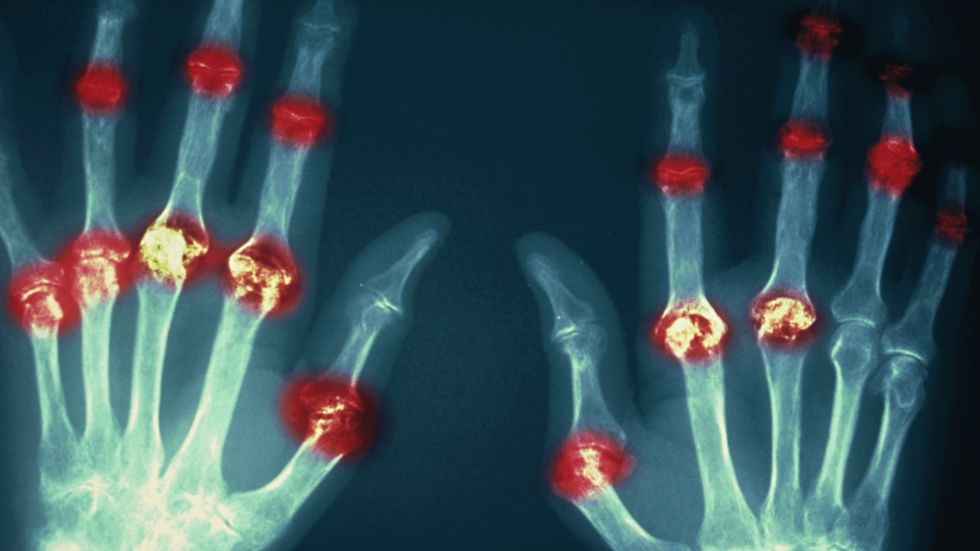

Rheumatoid arthritis can strike at any age